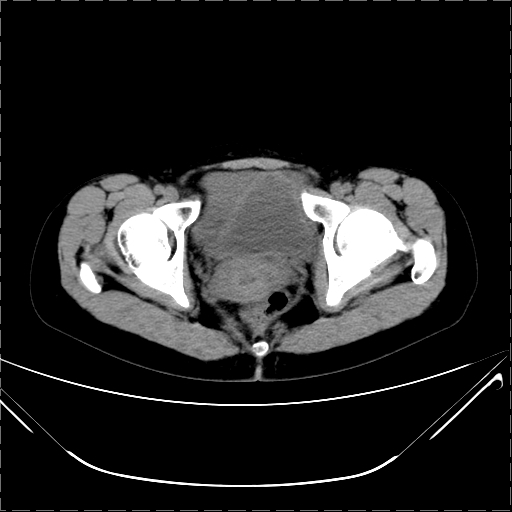

女 29岁 突然腹部疼痛1天 b超示子宫左后方肿块。月经正常。

请各位指教 该病人子宫周围云絮状高密度影是什么

影像表现复杂,膀胱上见一囊性包块,比膀胱密度高,其内有不均匀稍高密度,似与道格拉斯窝肿物无分界,病灶没有张力,因其腹平坦,推定其具有流动性,但又似见包膜,而b超没有报告这一现象。确实没见过。考虑卵巢囊肿蒂扭转并囊内出血可能。

病变主要位于道格拉斯窝,而且大体形态比较扁平且贴合子宫直肠,无明显张力及对周围脏器压迫,所以考虑为液体,而中间可见囊样病变伴环形强化,期内还可见分隔影,结合突发急性腹痛故多考虑囊腺瘤伴破裂出血。

腹腔镜术后 卵巢黄体囊肿破裂出血